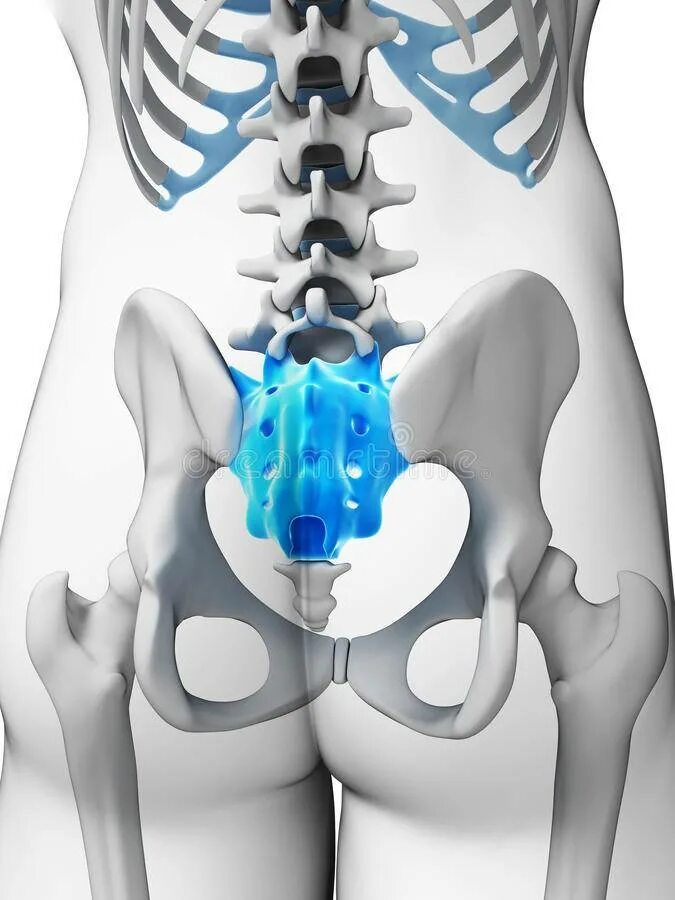

Пояснично крестцово копчиковый отдел